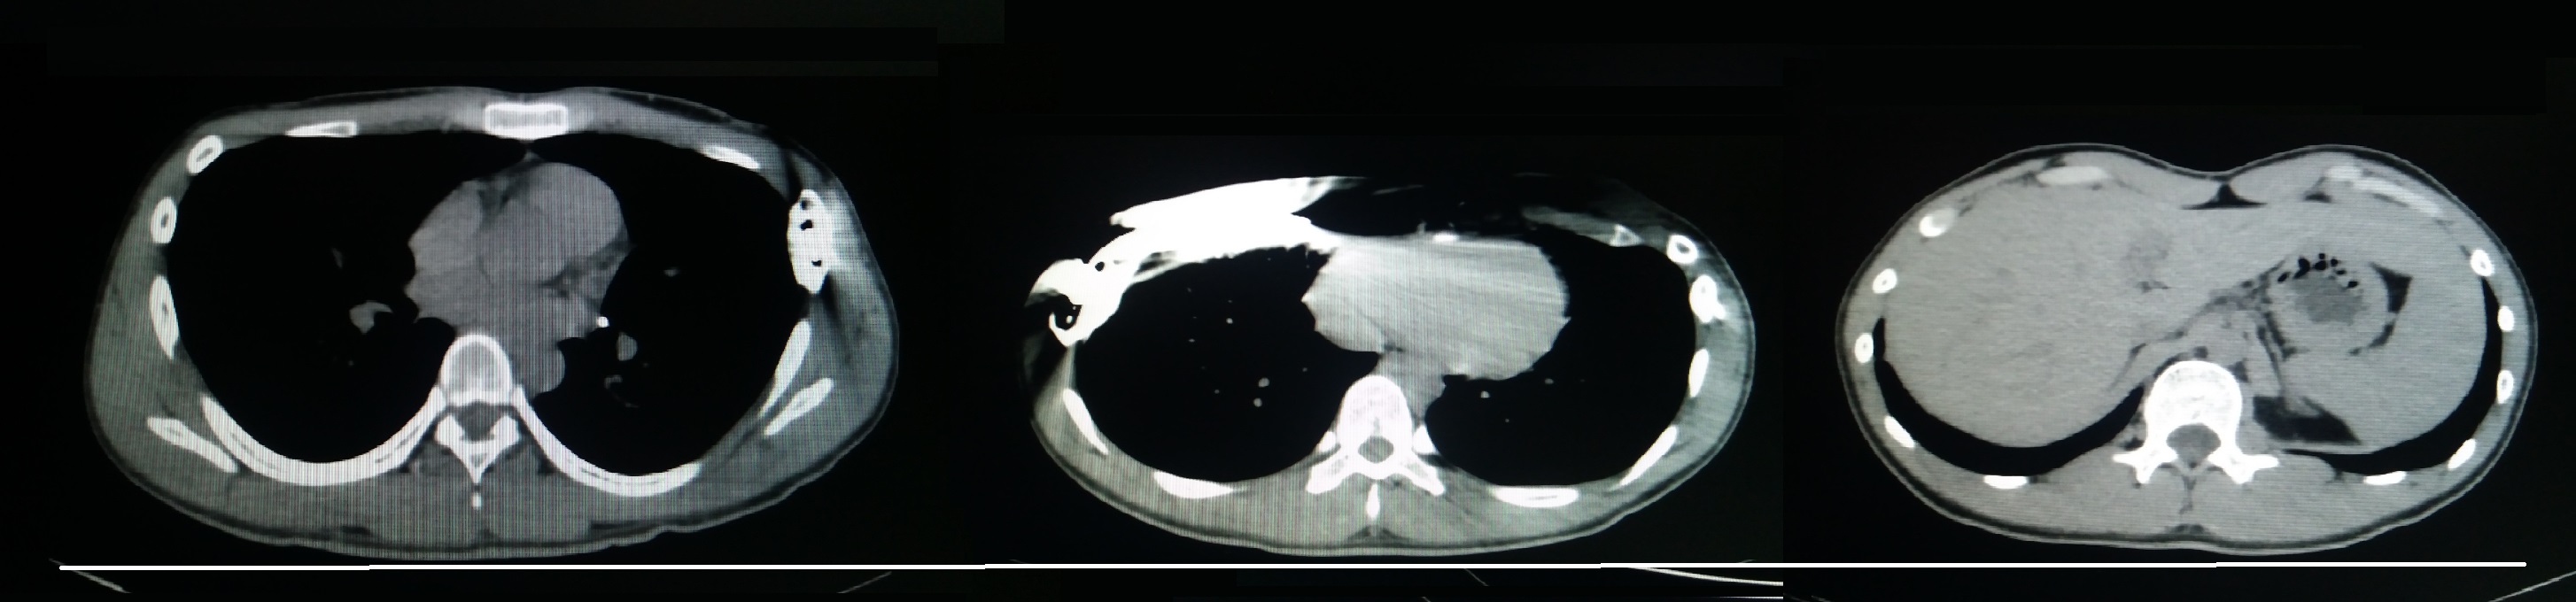

术前行X线检查:正位片提示胸壁内有钢板一条,钢板位置倾斜,脊柱轻度侧弯(图4)。侧位片提示前胸壁下部局部凹陷,钢板位置偏斜(图5)。行CT检查:可见胸壁内钢板影。横截面未见明显凹陷,但不同水平前后径明显不同(图6-10)。三维重建提示钢板影,前胸壁凹陷畸形(图11,12,13)。心电图及腹部超声检查未发现异常。

图6,CT横截面图:可见钢板伪影。

图7,CT横截面图:左侧胸壁钢板固定处。

图8,CT横截面图:右侧胸壁钢板固定处。

图18,沟状胸的CT特征。没有明显的中间凹陷,但不同水平的截面前后径不同。